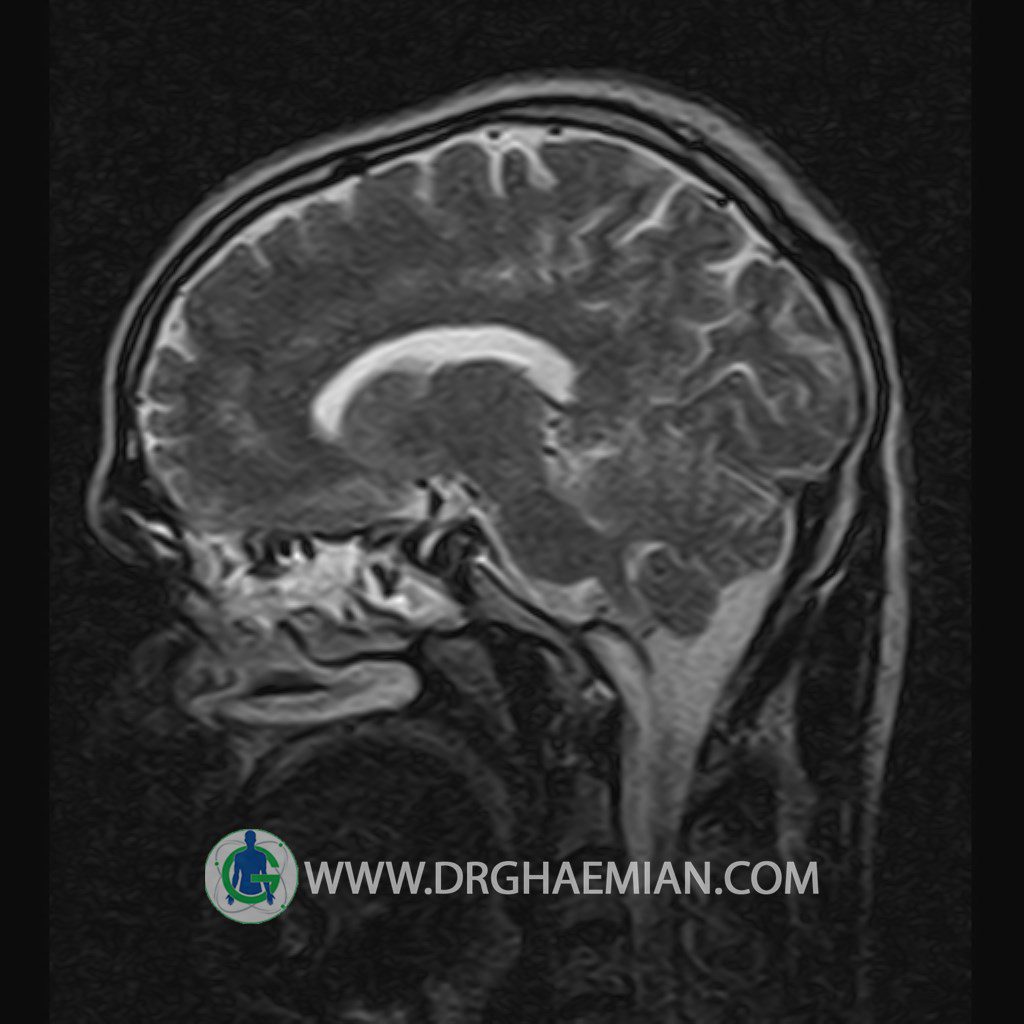

پزشکان اغلب از تصویربرداری ام آر آی برای تشخیص و درمان عارضه های پزشکی که فقط با استفاده از اشعه ایکس یا میدان مغناطیسی و امواج رادیویی قابل مشاهده است، استفاده می کنند. دستگاه ام آر آی تصاویر دقیق از ساختار های داخلی بدن ایجاد می کند. در این کیس یک میکروآدنوم در هیپوفیز بیمار مشاهده می شود.

HYPOPHYSIS MRI

(with and without contrast)

Technique: Axial , coronal T1 , Axial , coronal , sagittal T2 , Axial, coronal T1 post Gd & 64 dynamic thin coronal slices.

The infundibulum is centered and of normal size .

The optic chiasm and suprasellar spaces appear normal .

The cavernous sinus and imaged portions of the internal carotid artery and carotid siphon are unremarkable .

Evaluable portions of the neurocranium show no abnormalities .

The sphenoid sinus is clear and pneumatized .

Imaging of the hypothalamus after contrast medium administration was normal.

– Small hypoenhancing mass lesion ( 3 x 4 mm ) in posterior of pituitary stalk suggestive for micro adenoma

– Mucosal thickening in ethmoid & maxillary sinuses

is seen